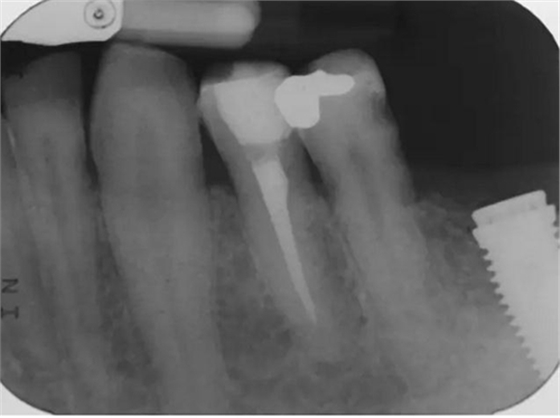

圖4 該病例中,左下4根充失敗,左下5牙髓壞死。兩個牙齒均需要根管治療和修復(fù)。

圖5 根管治療術(shù)后。左下4需要使用纖維樁,并用雙固化樹脂粘結(jié)劑粘結(jié)。左下5無需纖維樁。但2個牙齒均需要進(jìn)行覆蓋牙尖的修復(fù)。

圖7 術(shù)后片。左下4重新疏通。根尖4mm牙膠封閉,根管內(nèi)粘結(jié)了纖維樁。左下5根尖有根分叉。在根管冠段,可以樹脂(SDR)進(jìn)入,輔助固位。